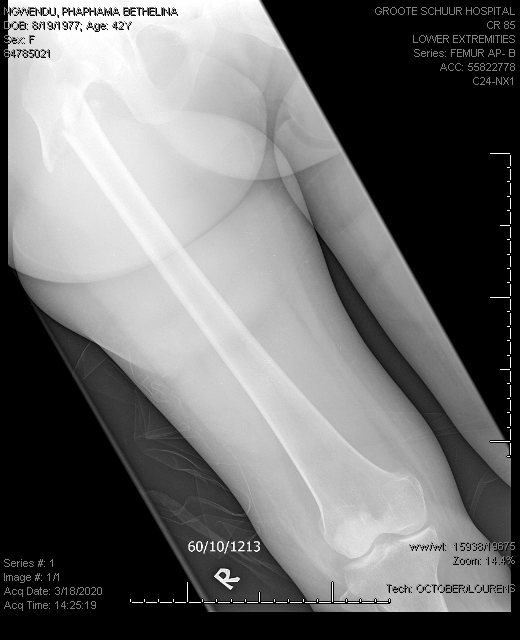

Calcium: blue; Magnesium: orange; Phosphate: grey

Reference ranges are the horizontal lines without dotted markers